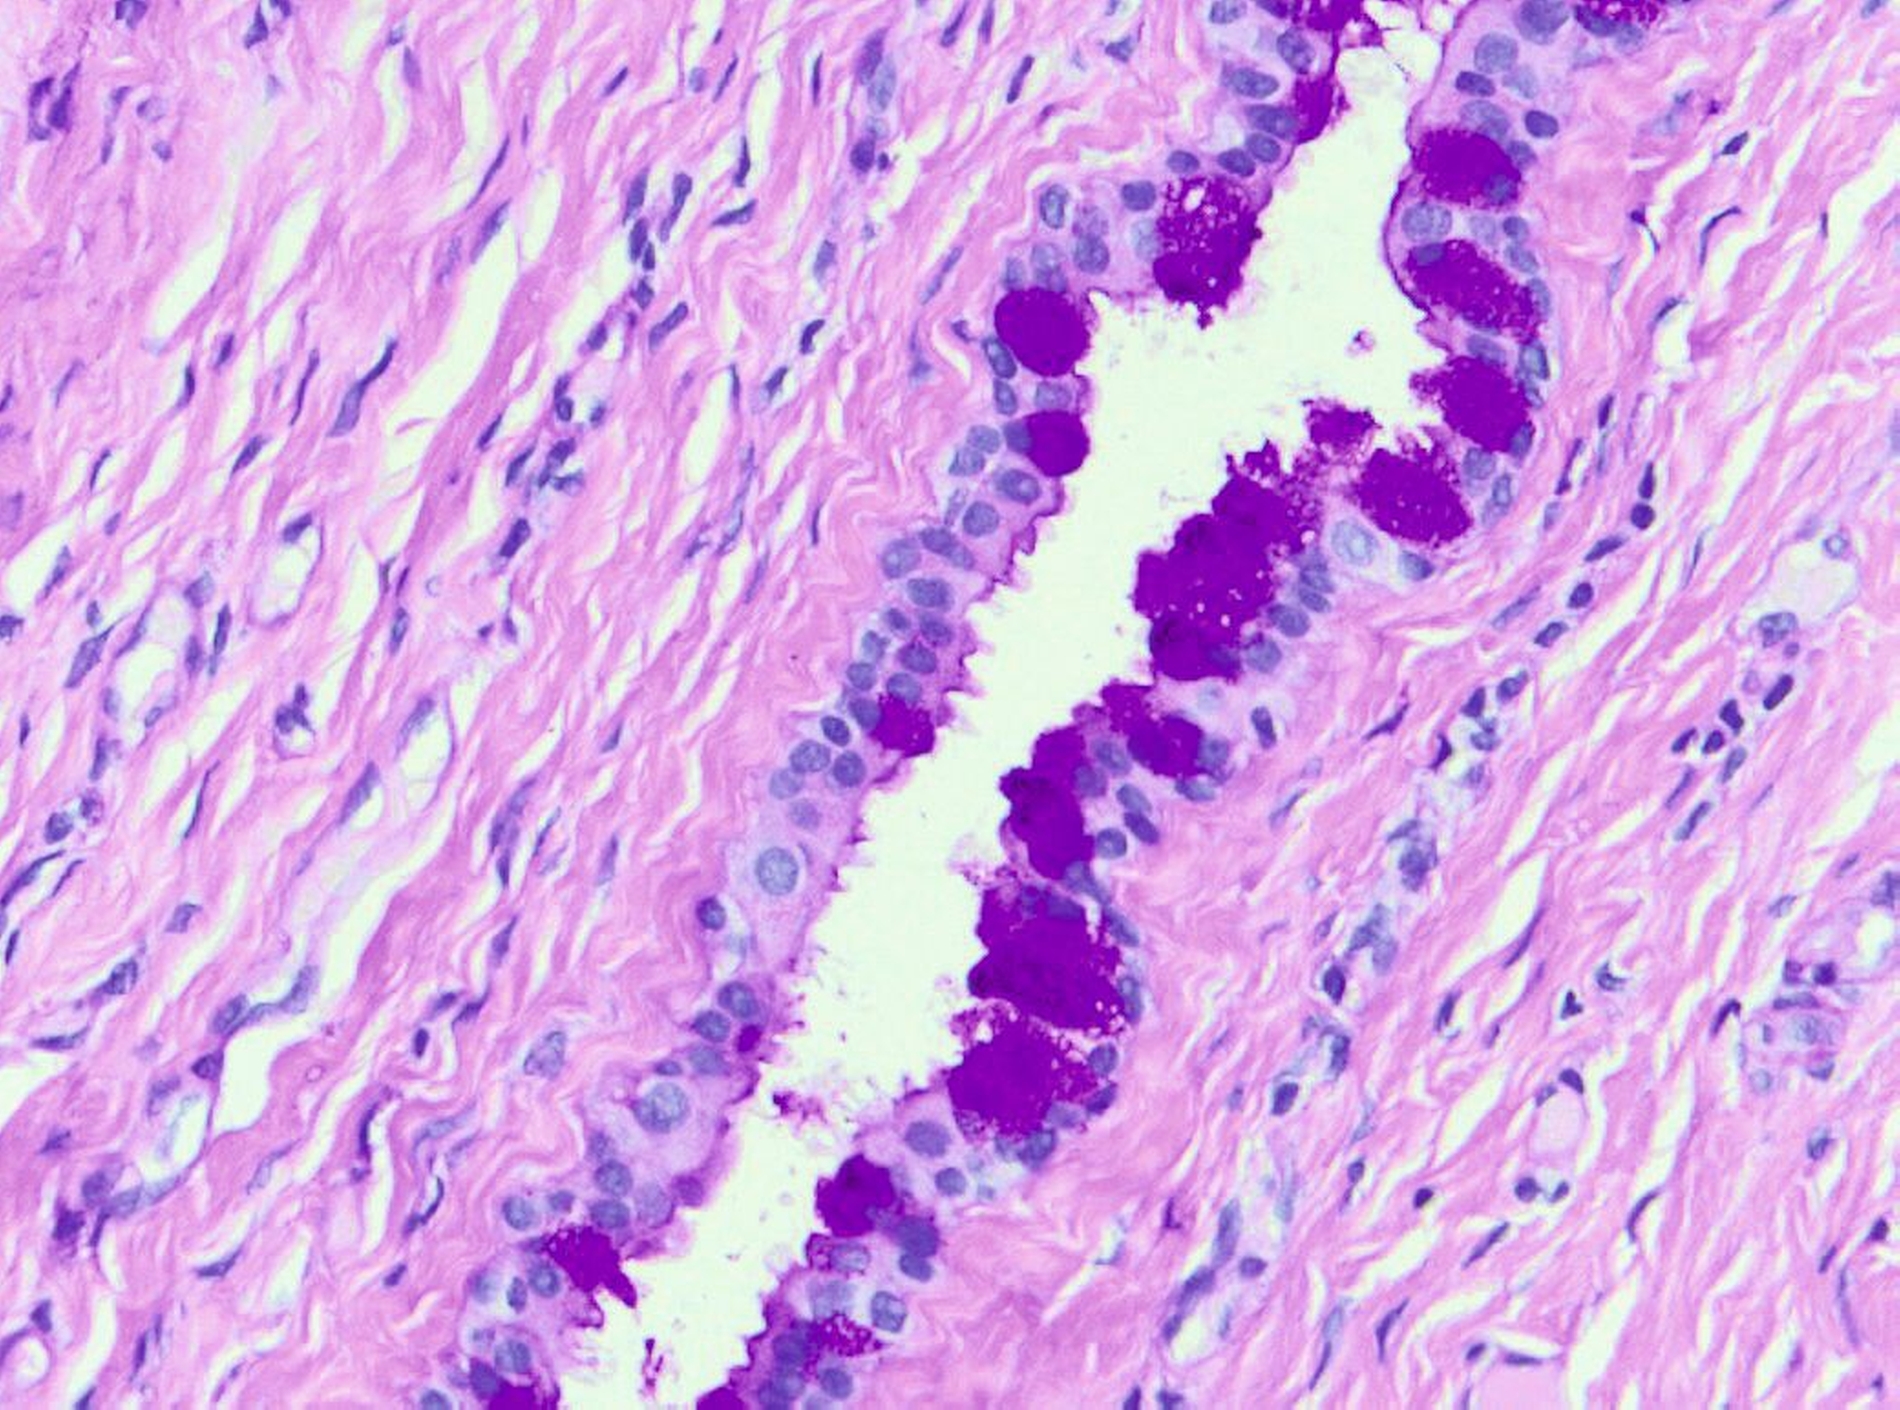

Im Ergebnis der pathohistologischen Begutachtung zeigten sich fibrosierte Zystenwandanteile, die mit respiratorischem Epithel ausgekleidet waren (Abbildung 3). Die zytologische Diagnostik des Punktats erbrachte ein zellloses, amorphes Sekret ohne atypische Zellelemente und ohne Anhalt für Malignität. Anhand der Klinik und des pathohistologischen Befunds wurde die Diagnose einer nasolabialen Zyste gestellt.

Der Zystenbalg hat häufig eine epitheliale Auskleidung mit Flimmerepithel und ist dadurch von entzündungsbedingten Zysten abgrenzbar.